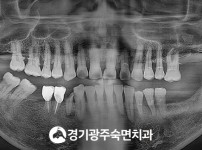

숙면임플란트 3개 - 스트라우만임플란트 (이*웅님)